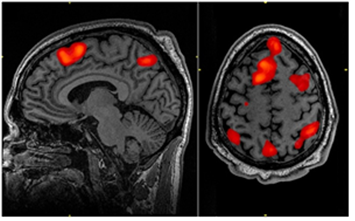

[그림 1] f-MRI 사진 [1]

한편, 여러분은 한번쯤 [그림 1]과 같은 뇌 사진을 보셨을 것입니다. 양전자단층촬영(PET)과 더불어 뇌기능을 알아보기 위해 흔히 사용되는 기능적자기공명영상(f-MRI)사진인데요. 외부 자극에 의해 활성화되어 산소나 양분을 공급하기 위해 혈류량이 변화하는 뇌의 영역을 구별되는 색깔로 나타내주고 있습니다. 이러한 신경촬영사진(neuroimage)을 보고 있노라면, 평소 우리 인간의 뇌는 고작 뇌 전체의 10~20% 정도에 불과한 극히 일부만을 사용하는 것 같습니다. 그러나 신경촬영에서는 과학자들이 통계적으로 정한 일정 수준 이상의 뇌 활동만이 표지된다는 점을 잊지 말아야 합니다. 실제로 어떤 특정 정보를 처리하는 과정에서 이에 관여하지 않는 뉴런들도 함께 발화하고 있다는 많은 증거들이 존재하기도 합니다. 즉, 일정 크기 이상의 조건을 충족할 만큼 수많은 대뇌 피질영역들이 동시에 활성화되고, 긴밀히 서로 연결됨으로써 비로소 의식이 가능케 된다는 것이지요.